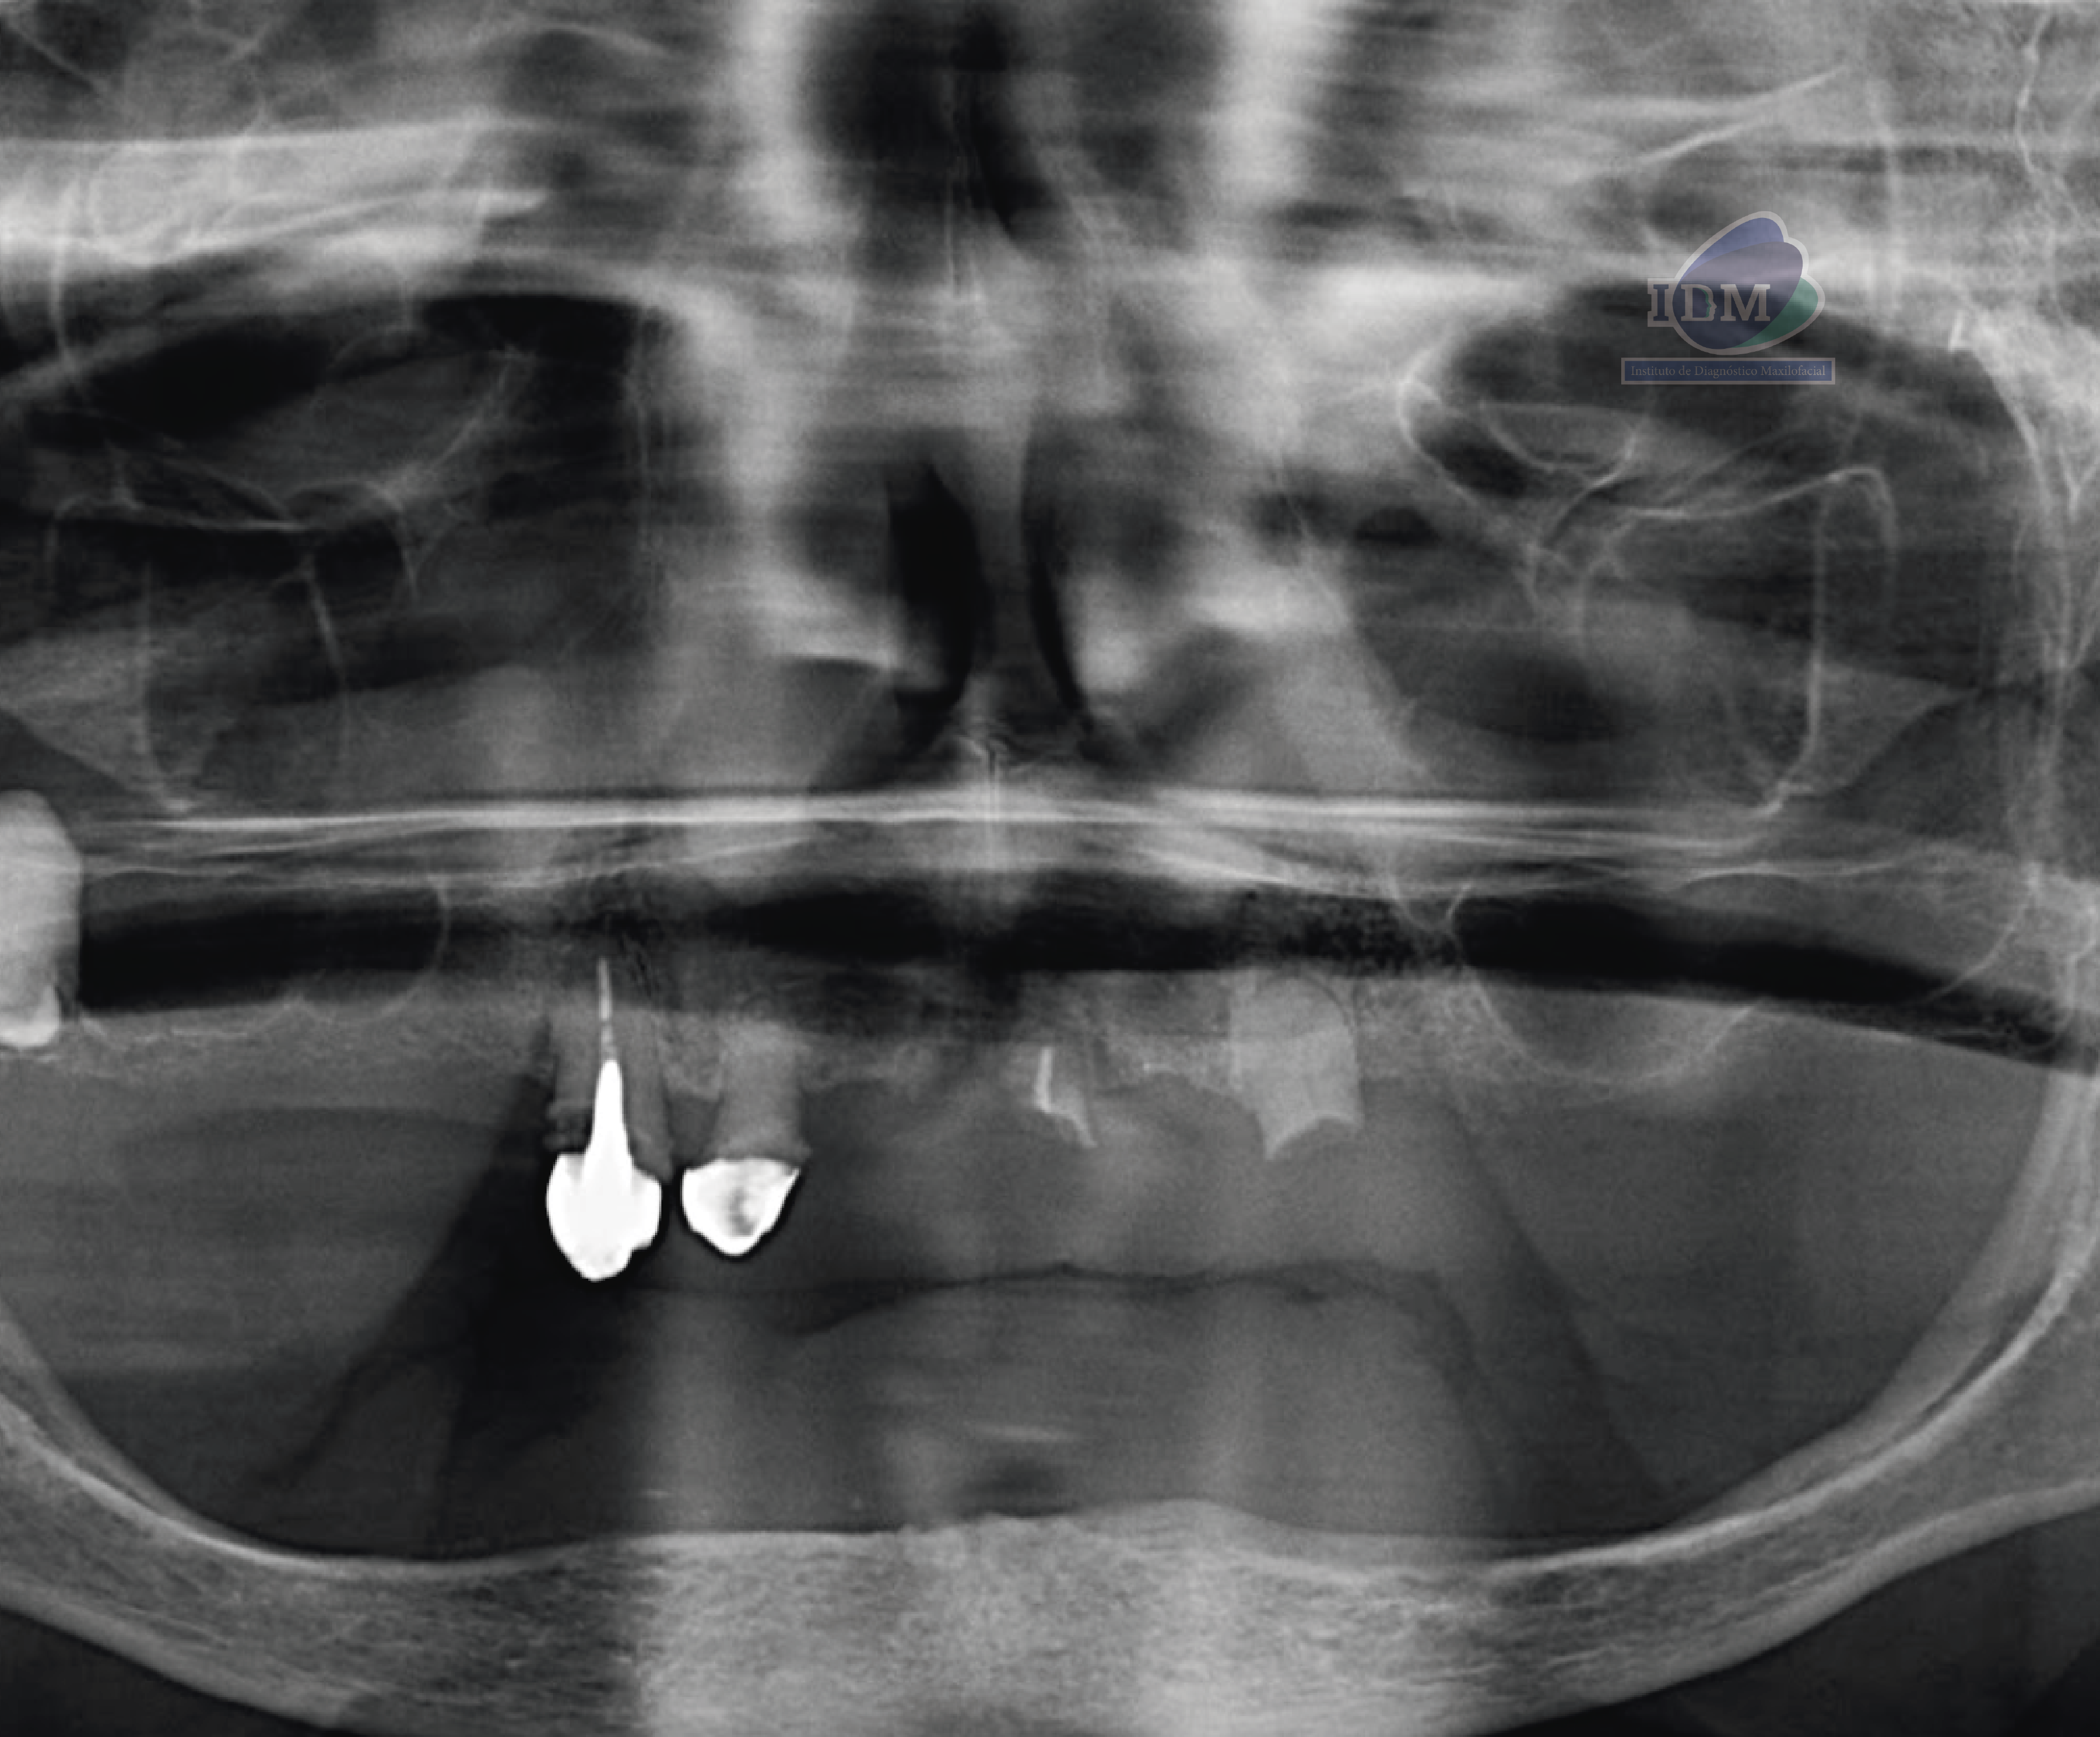

En la radiografía panorámica (Figura 1), se aprecia aplanamiento del contorno del cóndilo mandibular izquierdo, neumatización alveolar de los senos maxilares, edéntulo parcial en maxilar superior y edéntulo total en maxilar inferior, presencia de corona con falta de sellado, espigo y obturación sub extendida de conducto en pieza 13, corona protésica con falta de sellado en pieza 12, remanentes radiculares en piza 21 y 23. Siendo lo más resaltante la pieza 18, la cual esta retenida en posición vertical con un aumento de la densidad radicular.

A la evaluación de la tomografía volumétrica (CBCT) en los cortes axiales (Figura 2) y transaxiales (Figura 3), se aprecia pieza 18 orientada hacia vestibular y conducto permeable. Así mismo se evidencia hipercementosis con borramiento del espacio del ligamento periodontal.

CORTES TRANSAXIALES Y TANGENCIALES